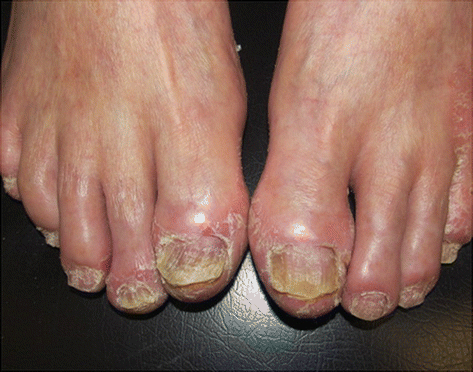

Fig. 3.3

Ungueal psoriasis. Archives of the Ambulatório de Psoríase, Pontifícia Universidade Católica de Campinas

Nail Psoriasis

The cupuliform depressions called pittings of the nails (thimble nails) are the most observed nail changes and occur due to changes of the proximal nail fold. The involvement of the nail plate can determine the appearance of subungual hyperkeratosis, onycholysis and “oil slicks” (brown band between onycholysis and lunula). The longitudinal ridges and onychodystrophy (Fig. 3.3) are caused by damage to ungueal matrix [11].